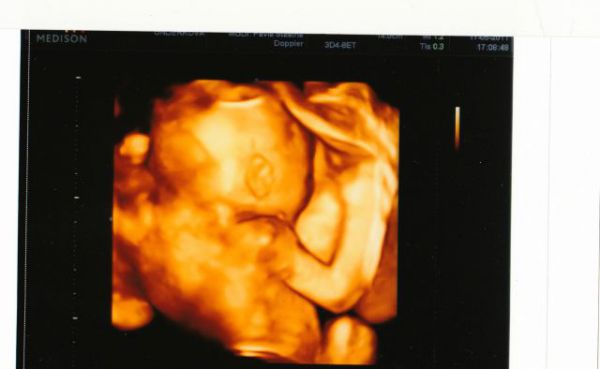

tak se mi poštěstilo vidět 3D utzv a naše milované miminko. Zatím je vše v pořádku a prý je to macík - 430 gr. nejdříve bylo k nám zády, pak se naštěstí umoudřilo a ukázalo se aspoň z profilu :-) jinak je to kluk jako buk :-) tak se všechny opatrujte :-) pááá